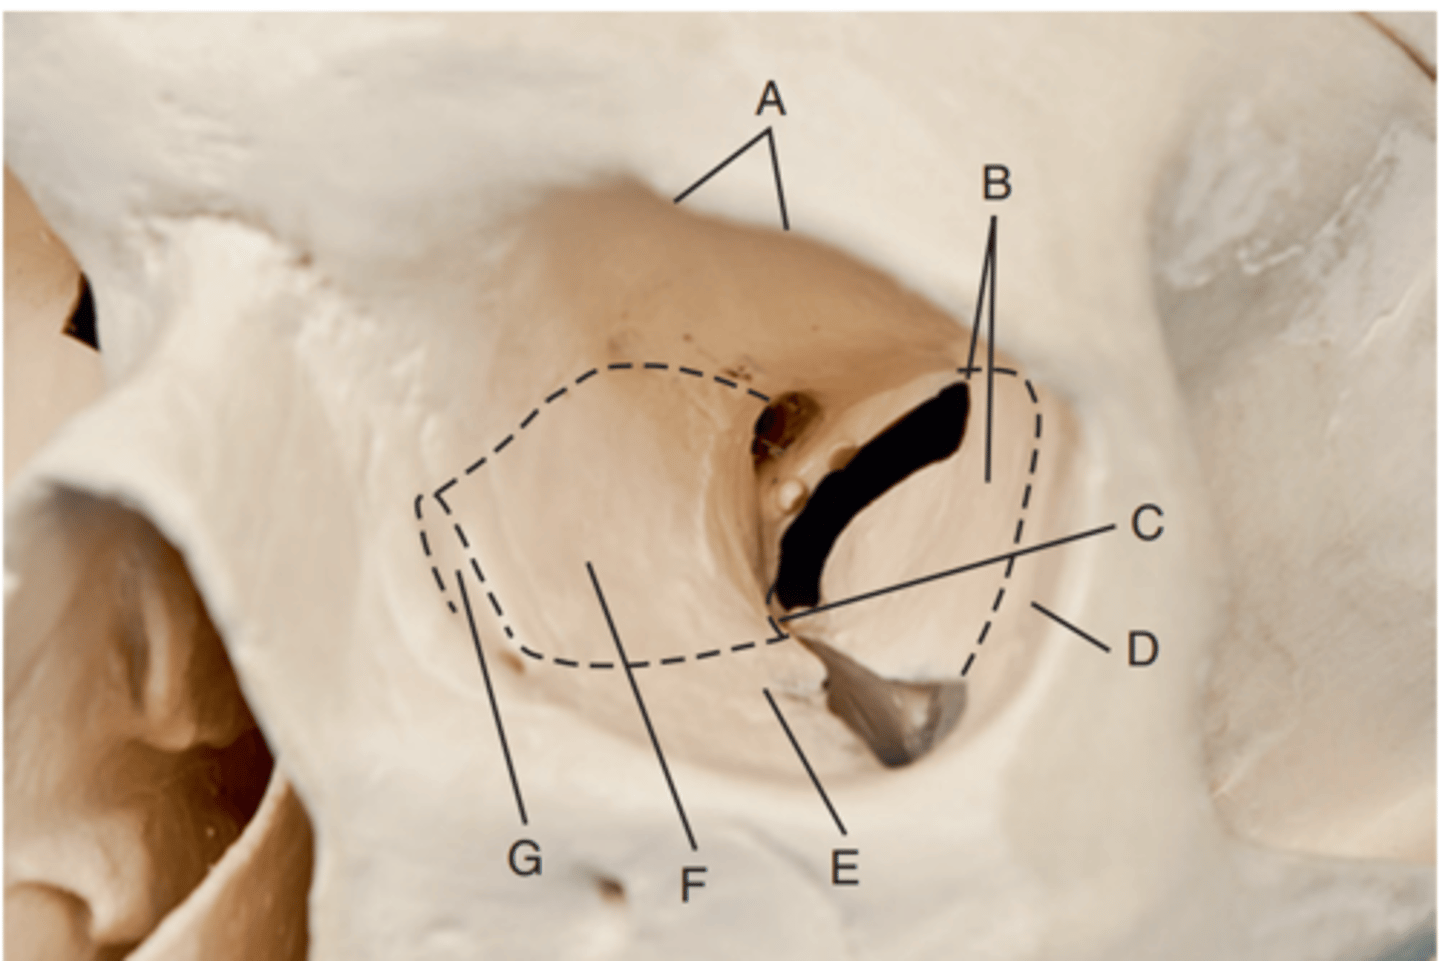

Optic foramen

Label A

Sphenoid strut

Label B

Superior orbital fissure

Label C

Inferior orbital fissure

Label D

Orbital plate of frontal bone

Label A

Sphenoid bone

Label B

Optic foramen and canal

Label C

Superior orbital fissure

Label D

Infraorbital margin (IOM)

Label E

Sphenoid strut

Label F

Lateral orbital margin

Label G

Supraorbital margin

Label H